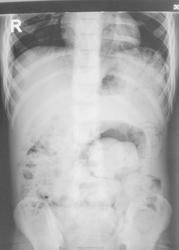

Подросток направлен на рентгенографию ОБП с диагнозом "Кишечная непроходимость".

Гиршпрунга?

С ТАКИМИ "завалами" вполне....

Явного "непрохода" нет. Вести консервативно, паралельно обследовать...подумать и об ирригоскопии...

А что вообще со стулом? Запоры с детства? Или нормальный?

Запоры с детства.

Барий дан в четверг п/о, последний снимок "от сегодня", следовательно "пассаж" следовал почти пять дней.

Без ирригоскопии не обойтись, полагаю. Необходимо показать зону аганглиоза.

У Филипкиной есть монография по толстому кишечнику. Точное название не скажу. Есть там точно такая картинка , да  и мне такие в гастроотделении облдетбольницы часто приходилось описывать- так выглядит  левосторонний микстоколон. Когда  врожденное увеличение  нисходящего отдела ободочной кишки. Запоры - с детства. Иногда отстают в росте .При ирригографии- задержка контраста именно там , гда на обзоре - завалы. Их перед ирригорафией клизмами с магнезие ( кажется) приходится дня три "отмывать " , чтобы хорошо стала  была видна  стенка кишечника. Контуры рельефа- обычно- огрублены. Гаустрация- сглажена.